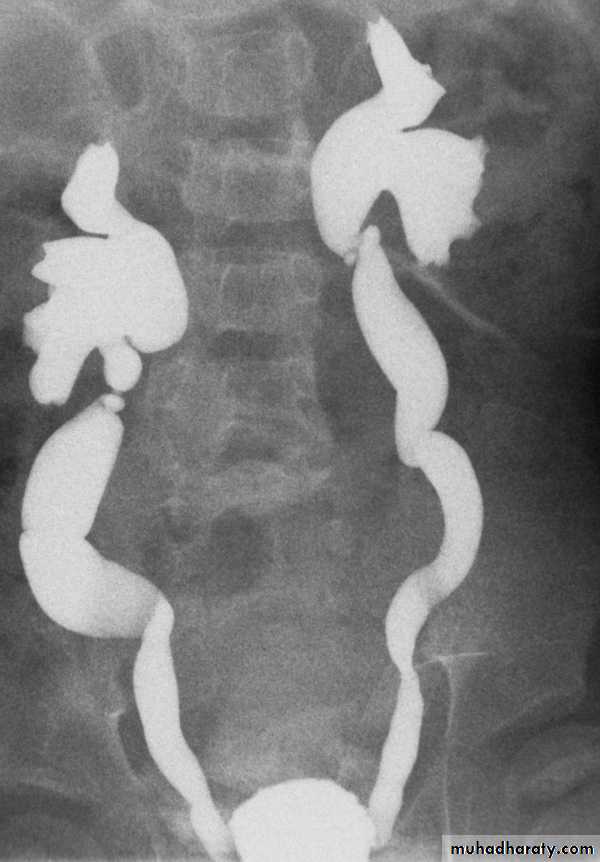

14- Retrocaval

16- Retrocaval